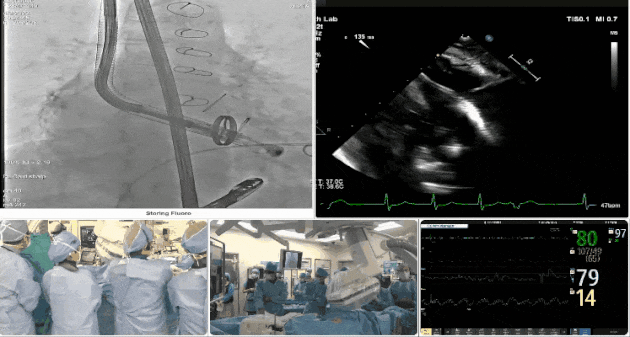

第三例患者手術(shù)難點(diǎn)

1、心率慢(<50bpm),術(shù)后起搏器植入風(fēng)險(xiǎn),術(shù)前需評(píng)估心電圖情況;2、CT顯示主動(dòng)脈瓣機(jī)械瓣置換術(shù)后,需明確三尖瓣是否同期做過(guò)修復(fù)。

術(shù)中TEE觀(guān)察夾持件的位置

術(shù)后DSA

術(shù)后超聲評(píng)估瓣膜穩(wěn)定性良好,無(wú)瓣周漏

手術(shù)過(guò)程

術(shù)者采用經(jīng)右側(cè)頸靜脈入路的方式將輸送器送入患者心臟內(nèi),在TEE及DSA引導(dǎo)下調(diào)整輸送器頭端角度,使得輸送器與三尖瓣瓣環(huán)平面垂直。在輸送器進(jìn)入右心室后釋放室間隔錨定裝置,而后釋放瓣葉夾持件(2個(gè)耳片結(jié)構(gòu))成垂直狀態(tài)。在TEE及DSA確定夾持件固定至三尖瓣葉根部且位于右室側(cè)后釋放人工瓣心房側(cè)盤(pán)片。隨后調(diào)整瓣膜同軸性以及室間隔錨定件位置(貼合室間隔),前推藏針管并固定,進(jìn)而釋放室間隔錨定裝置,并再次確認(rèn)瓣膜位置、穩(wěn)定性及同軸性,合攏輸送鞘后撤出輸送器,最終順利完成LuX-Valve Plus人工三尖瓣瓣膜的植入。